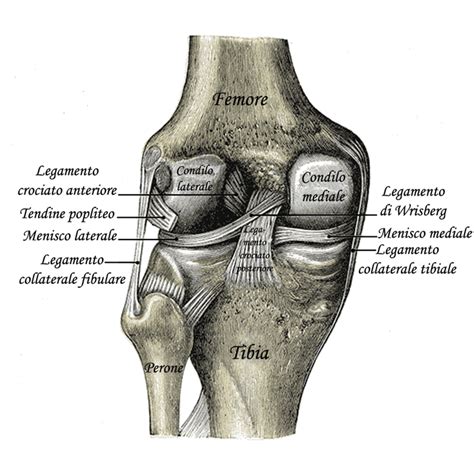

Pochi giorni prima dell'inizio delle gare olimpiche, la sfortuna ha colpito nuovamente. Lindsey Vonn ha subito una completa rottura del legamento crociato anteriore (LCA) del ginocchio sinistro durante una gara di Coppa del Mondo a Crans-Montana, in Svizzera. Questo tipo di infortunio, che solitamente comporta una forte instabilità articolare, richiede mesi di sospensione dall'attività agonistica e spesso un intervento chirurgico per ripristinare la stabilità.

Il Rischio Clinico e la Fisiologia del Ginocchio Senza LCA

Dal punto di vista clinico, competere con un legamento crociato completamente rotto è considerato estremamente rischioso. Il LCA gioca un ruolo cruciale nella stabilità anteriore del ginocchio e nel controllo dei movimenti rotazionali. La sua assenza altera profondamente la meccanica articolare, aumentando il carico su altri legamenti e sulla cartilagine. In queste condizioni, la stabilità è affidata quasi esclusivamente alla forza muscolare e al controllo neuromuscolare. Sebbene i tutori possano fornire un certo grado di stabilità, non sono in grado di sostituire completamente la funzione biomeccanica del legamento. Medici ed esperti di medicina dello sport hanno definito la scelta di Vonn "rischiosa ma possibile" solo in casi eccezionali, come quello di atleti d'élite con un controllo neuromuscolare superiore alla media e con significativi compensi muscolari a carico dei quadricipiti e dei muscoli posteriori della coscia.